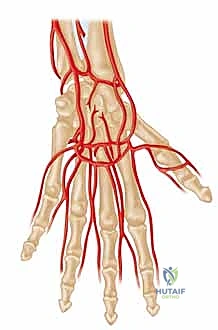

Arterial Architecture and the Palmar Arches

Before a single incision is conceptualized, an exhaustive mastery of the hand's vascular architecture is paramount; in this anatomical theater, precision is synonymous with prevention. The primary arterial inflow to the hand is derived from the radial and ulnar arteries, which originate from the bifurcation of the brachial artery at the antecubital fossa. The ulnar artery, typically the dominant vessel, courses distally to form the superficial palmar arch, located superficially within the mid-palm, deep only to the palmar aponeurosis. This arch serves as the major arterial conduit supplying the ulnar aspect of the digits, giving rise to the common digital arteries.

The radial artery, after traversing the anatomical snuffbox and piercing the first dorsal interosseous muscle, primarily forms the deep palmar arch. This structure lies more proximally and deeply within the palm, resting directly upon the metacarpal bases and interosseous muscles, and predominantly supplies the radial aspect of the hand, including the thumb and index finger. In approximately 80% of the patient population, these two arches are in continuous communication, forming a complete palmar arch system that provides robust, redundant collateral circulation. However, the presence of an incomplete arch significantly amplifies the risk of catastrophic ischemia should one primary inflow vessel become compromised. Furthermore, anatomical variants such as a persistent median artery—which accompanies the median nerve through the carpal tunnel—can contribute significantly to digital perfusion and must be identified during preoperative mapping.

Neurovascular Relationships and Sympathetic Innervation

The regulation of vascular tone in the upper extremity is dictated by sympathetic nerve fibers that originate in the spinal cord, typically exiting via the second and third thoracic nerve roots. These preganglionic fibers synapse in the sympathetic chain, and postganglionic fibers traverse the brachial plexus, ultimately distributing along the major arterial trunks. Critically for the hand surgeon, these sympathetic fibers do not travel as distinct, isolated nerves in the distal extremity; rather, they are intricately embedded within the adventitial layer of the arteries themselves.

As the common digital arteries bifurcate into the proper digital arteries, they are intimately accompanied by the proper digital nerves, forming the neurovascular bundles of the digits. This relationship is of profound surgical significance. During a digital sympathectomy, the primary objective is the meticulous excision of this adventitial layer to disrupt sympathetic signaling. Because the adventitia is physically contiguous with the surrounding connective tissue and lies mere millimeters from the digital nerve, extreme microsurgical dexterity is required to achieve complete adventitial stripping without inflicting iatrogenic neuropraxia or structural damage to the arterial media.